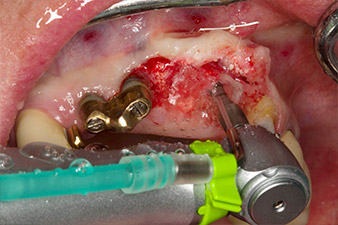

la perforazione pilota è eseguita con il nuovo dispositivo Implatmed e il manipolo contrangolo Ws-56L

Fig. 2: Due mesi dopo si è eseguita perforazione pilota con il nuovo motore Implantmed e il manipolo contrangolo WS-56L (programma P1, velocità 1:1). Il raffreddamento avviene con il tubo spray posizionato sulla sinistra (per utenti destrorsi).